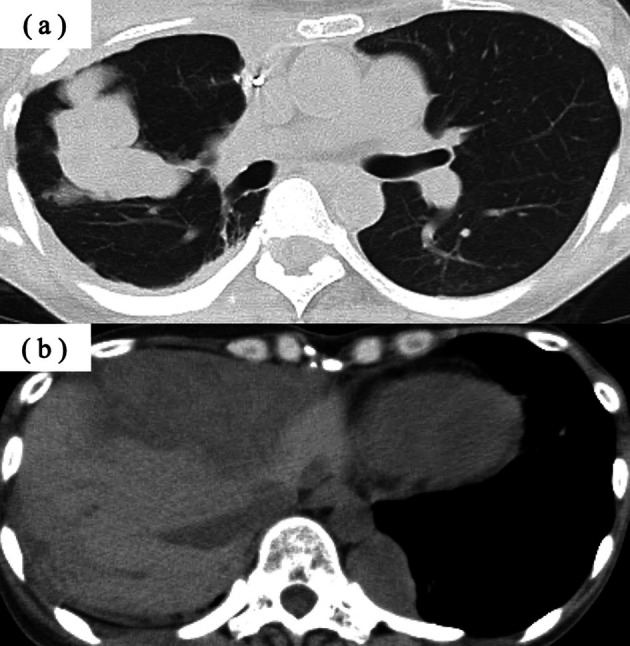

一位47岁的女性在13年前被诊断出患有侵袭性胸腺瘤。她经历了多次手术,以及化疗和放疗。患者出现正红细胞性贫血后,对反复输血无反应,化疗停止。骨髓活检结果显示纯红细胞发育不全(PRCA)。环孢素治疗可改善PRCA;然而,患者3年后死于侵袭性肺炎球菌感染。胸腺瘤相关的PRCA的发病仍然是不可预测的,两种情况的诊断之间可能会出现明显的延迟。

A 47-year-old woman was diagnosed with invasive thymoma 13 years ago. She had undergone repeated surgeries, as well as chemotherapy and radiation therapy. Chemotherapy was discontinued after the patient developed normocytic anemia, which was unresponsive to repeated blood transfusions. Bone marrow biopsy results revealed pure red cell aplasia (PRCA). Cyclosporine treatment led to improvement in PRCA; however, the patient died 3 years later from an invasive pneumococcal infection. The onset of thymoma-associated PRCA remains unpredictable, and a significant delay may occur between the diagnosis of the two conditions.